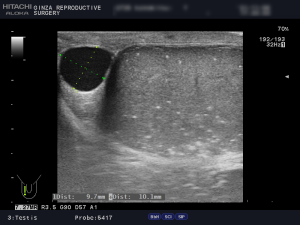

(例)左右の精巣のエコー画像です。

精巣内に腫瘍はありませんが、左右の精巣に白い点が多数見えます。これは精巣機能低下により石灰化してきています。

また、右側に精液瘤9.7mm × 10.1mmがあります。こちらは治療してしますと精巣機能低下につながるので、不妊治療中の場合は、経過観察です。

更に、精巣の大きさに左右差があるのが分かります。左側16ml、右側20mlで、精索静脈瘤により、左側が萎縮しています。